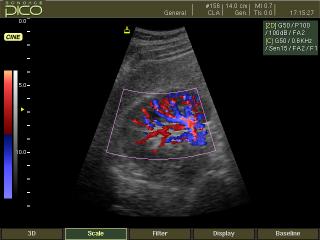

Kidney, color doppler

SonoAce-Pico. Kidney, color doppler.